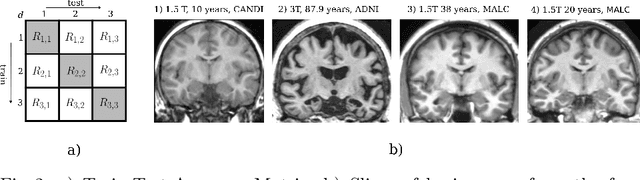

Abstract:The ability of neural networks to continuously learn and adapt to new tasks while retaining prior knowledge is crucial for many applications. However, current neural networks tend to forget previously learned tasks when trained on new ones, i.e., they suffer from Catastrophic Forgetting (CF). The objective of Continual Learning (CL) is to alleviate this problem, which is particularly relevant for medical applications, where it may not be feasible to store and access previously used sensitive patient data. In this work, we propose a Continual Learning approach for brain segmentation, where a single network is consecutively trained on samples from different domains. We build upon an importance driven approach and adapt it for medical image segmentation. Particularly, we introduce learning rate regularization to prevent the loss of the network's knowledge. Our results demonstrate that directly restricting the adaptation of important network parameters clearly reduces Catastrophic Forgetting for segmentation across domains.